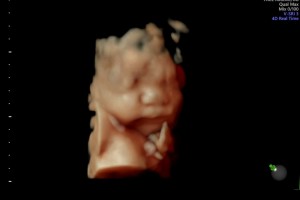

30주 입체초음파입니다 :)

이레IYRAE

2025-08-21